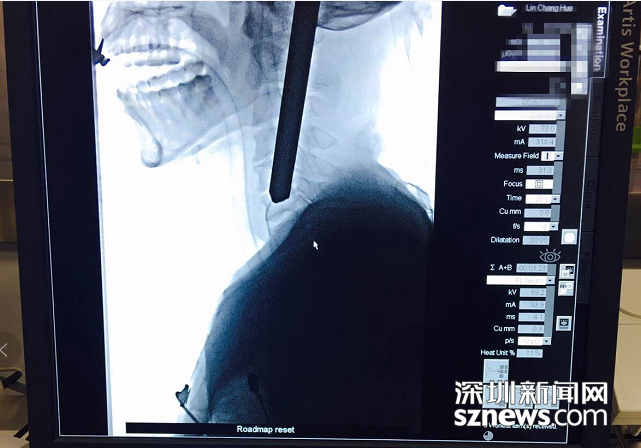

拍片显示钢筋深入患者颈部

深圳新闻网7月24日讯(记者 刘梦婷 通讯员 李梦园)7月21日清晨7时许,46岁的建筑工人张先生遭遇一场横祸,他在工地行走时不慎摔倒,被一根长约75cm、粗约2cm的钢筋从左侧颈部插入,右侧头顶部穿出,穿透脑袋。

北大深圳医院接诊后立即组织多学科会诊,同时开通颅脑外伤绿色通道。消防员先行将伤者的颅外钢筋切除,随后,神经外科紧急行脑血管造影。考虑到钢筋对大脑及脑血管可能造成的损伤,神经外科团队决定立即为患者施行手术。